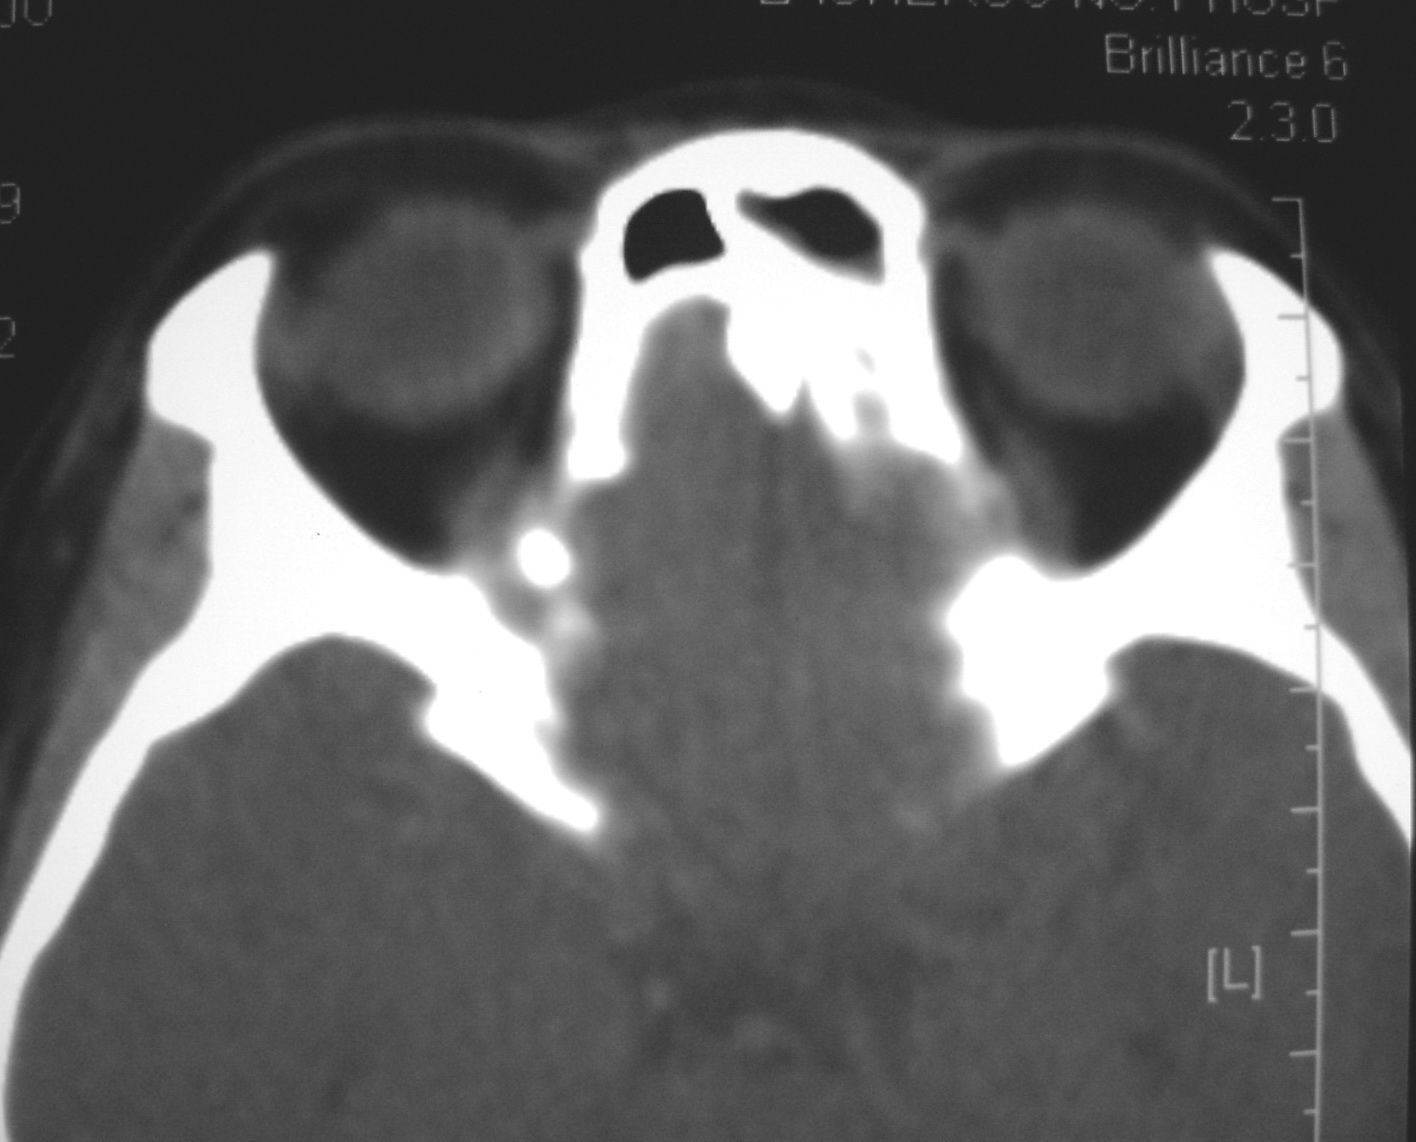

右侧眼眶脂肪瘤

女,34岁。右眼不适半年。

会员诊断:

表皮样囊肿、皮样囊肿、脂肪瘤

手术病理

:右侧眼眶

脂肪瘤

。